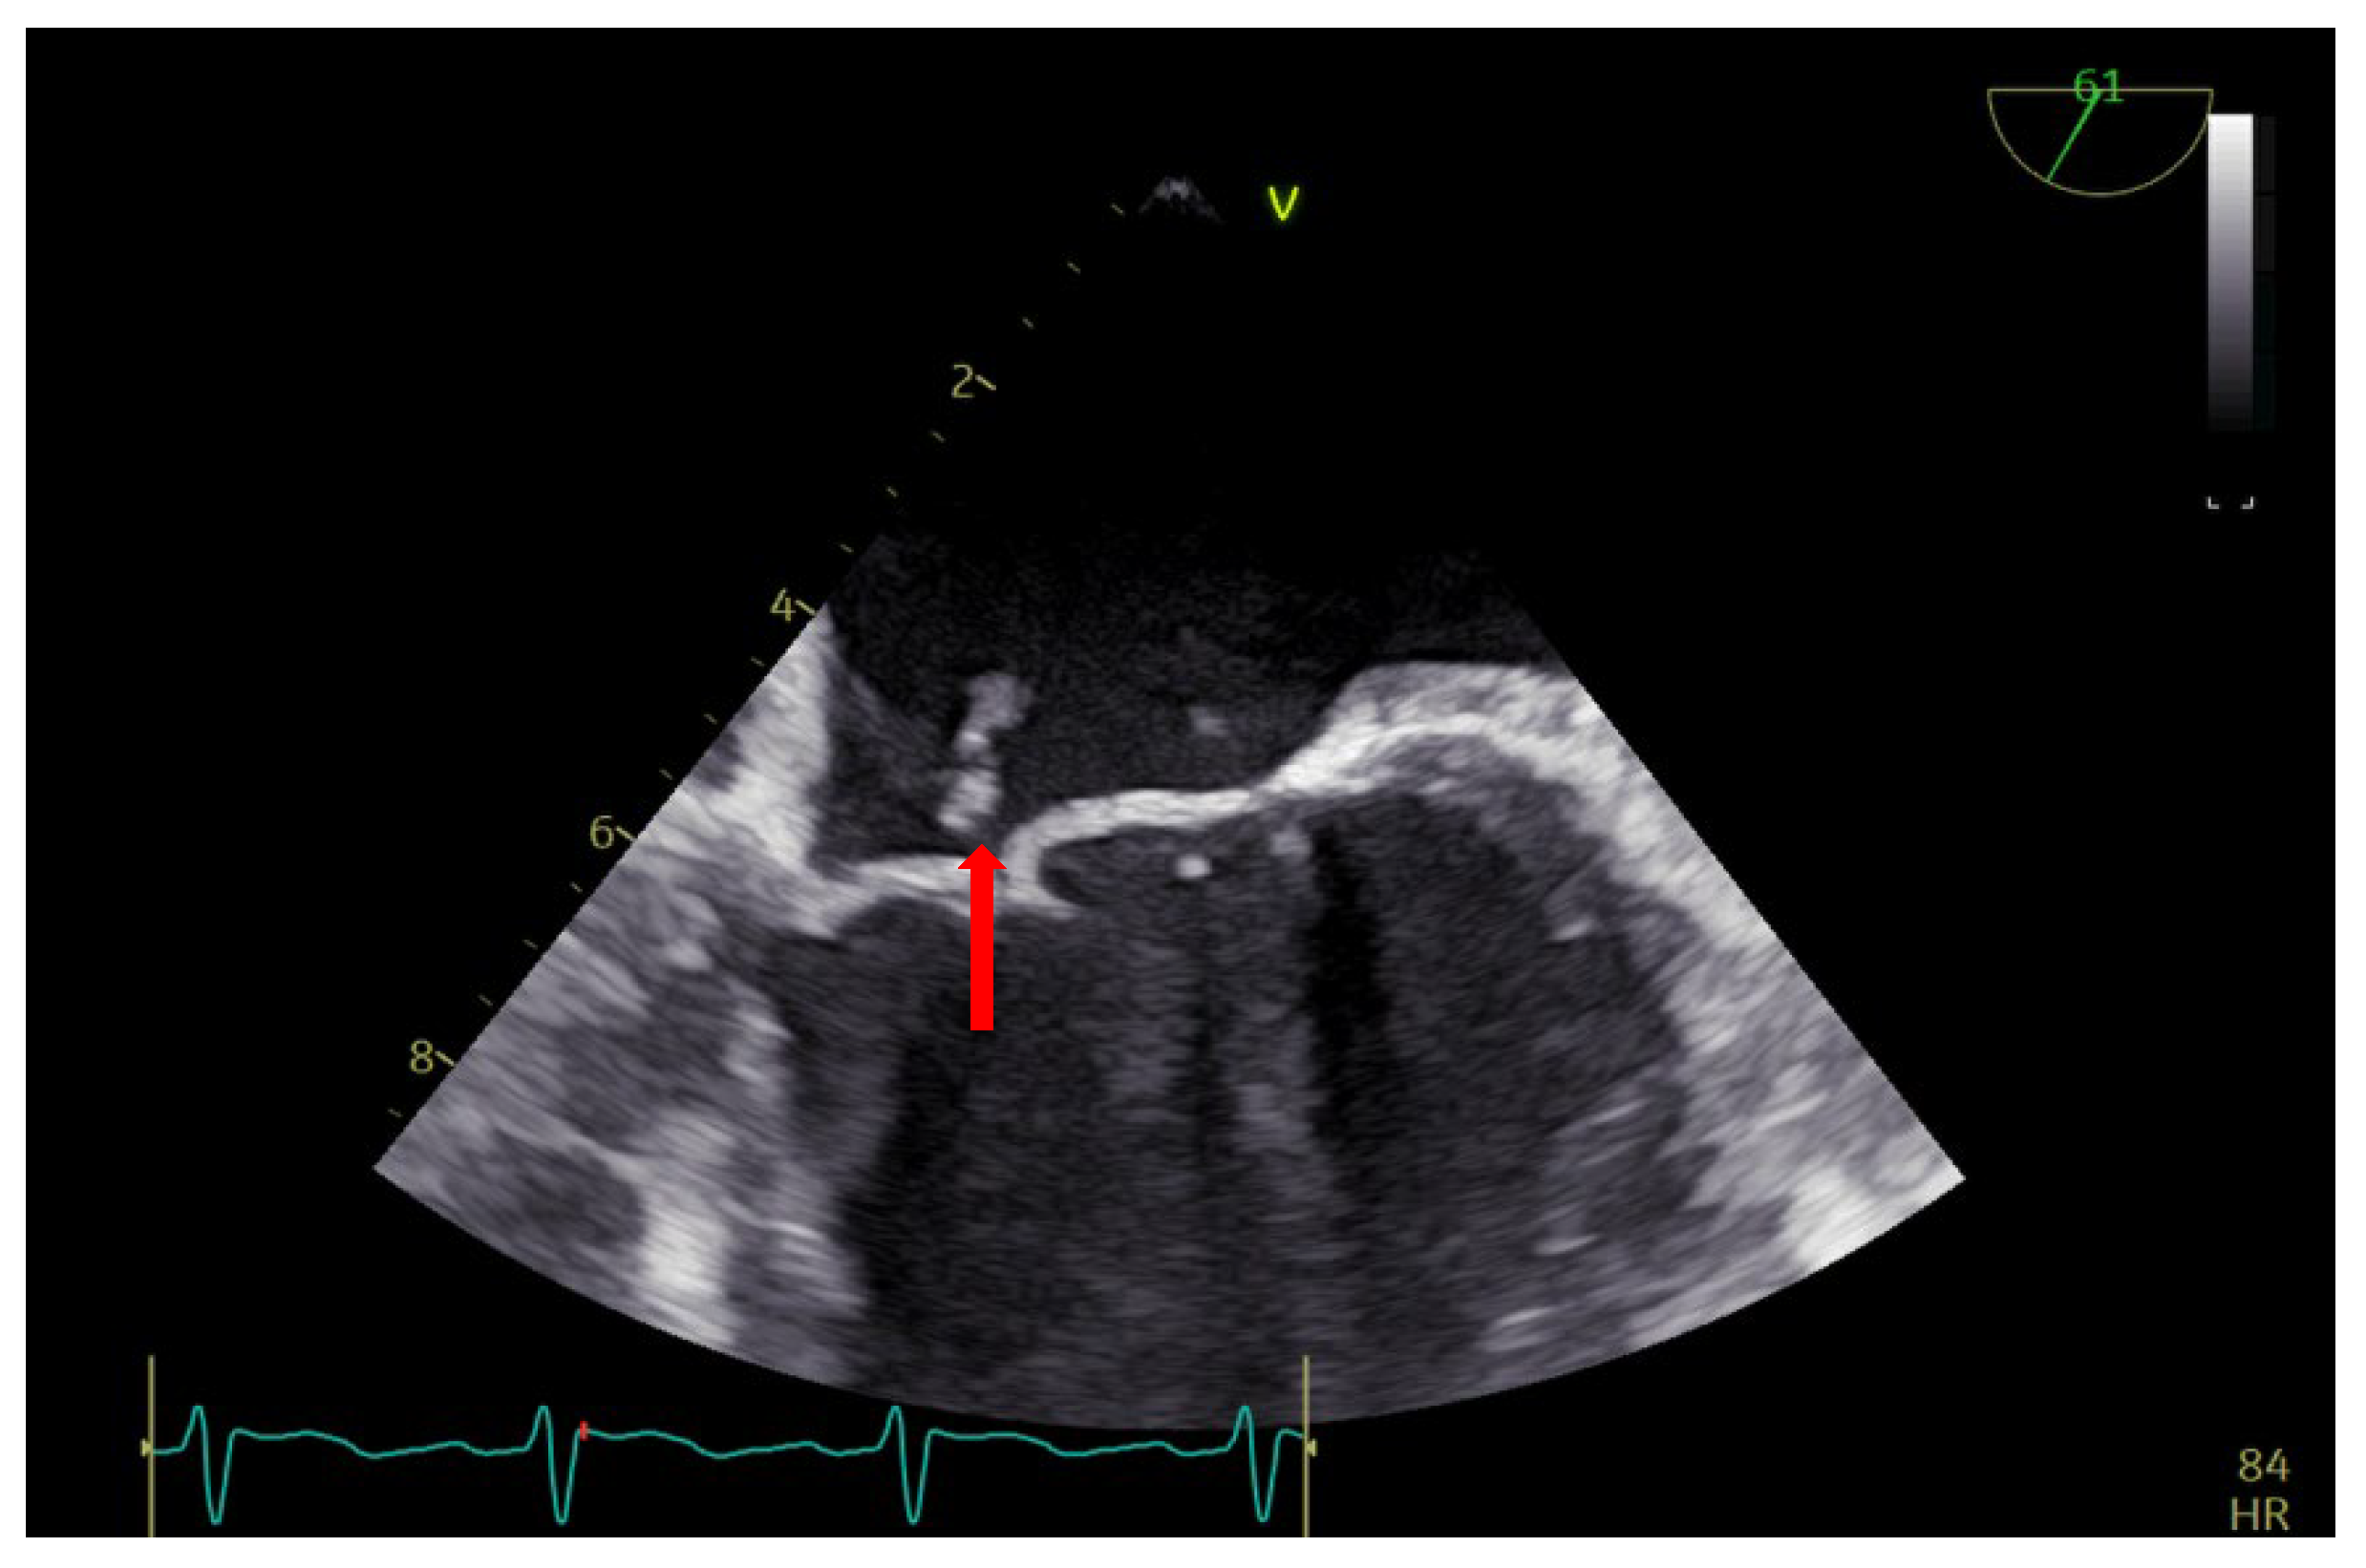

2. Case Report